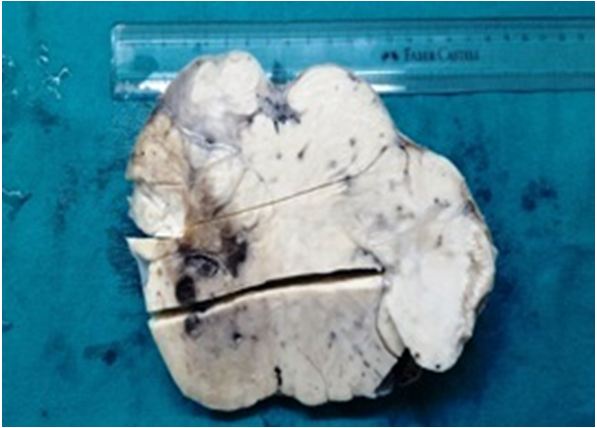

Uterine Myxoid Leiomyosarcoma Associated with Multiple Myomata in a Fertile Woman: A Case Report

Journal of Oncology Research and Therapy